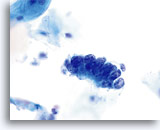

Biopsie

Papillär-seröses Endometriumkarzinom

Gleiche Patientin, gesplittetes Zellmaterial

Biopsie

Papillär-seröses Endometriumkarzinom

Gleiche Patientin, gesplittetes Zellmaterial